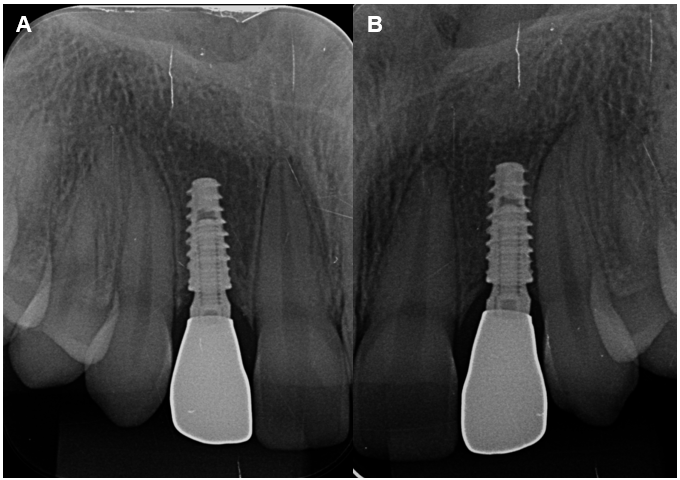

A etapa seguinte envolveu a instalação dos implantes após a averiguação do indicador de posição e o Osstell Beacon® foi utilizado para verificar a estabilidade do implante. Foi utilizado um cicatrizador, pois é um sistema de carga precoce e não imediata e realizada a radiografia periapical.

Após o período de osseointegração, foi realizada uma nova radiografia e foi observada a neoformação óssea ao redor do implante. Nessa etapa também foi realizada a reabertura com a captura de provisórios que têm a função de remodelar o tecido peri-implantar, sendo primordial para o perfil de emergência.

As coroas metalocerâmicas foram instaladas e as radiografias periapicais realizadas.